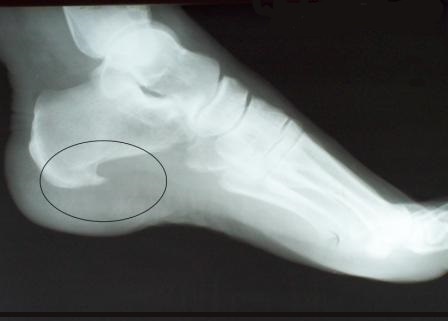

В результате постоянного взаимодействия и травмирования от неправильной нагрузки в области пяточной кости формируется кальцифицированный вырост - остеофит, который, по сути, и будет являться пяточной "шпорой". Он давит на окружающие ткани стопы и вызывает боли.